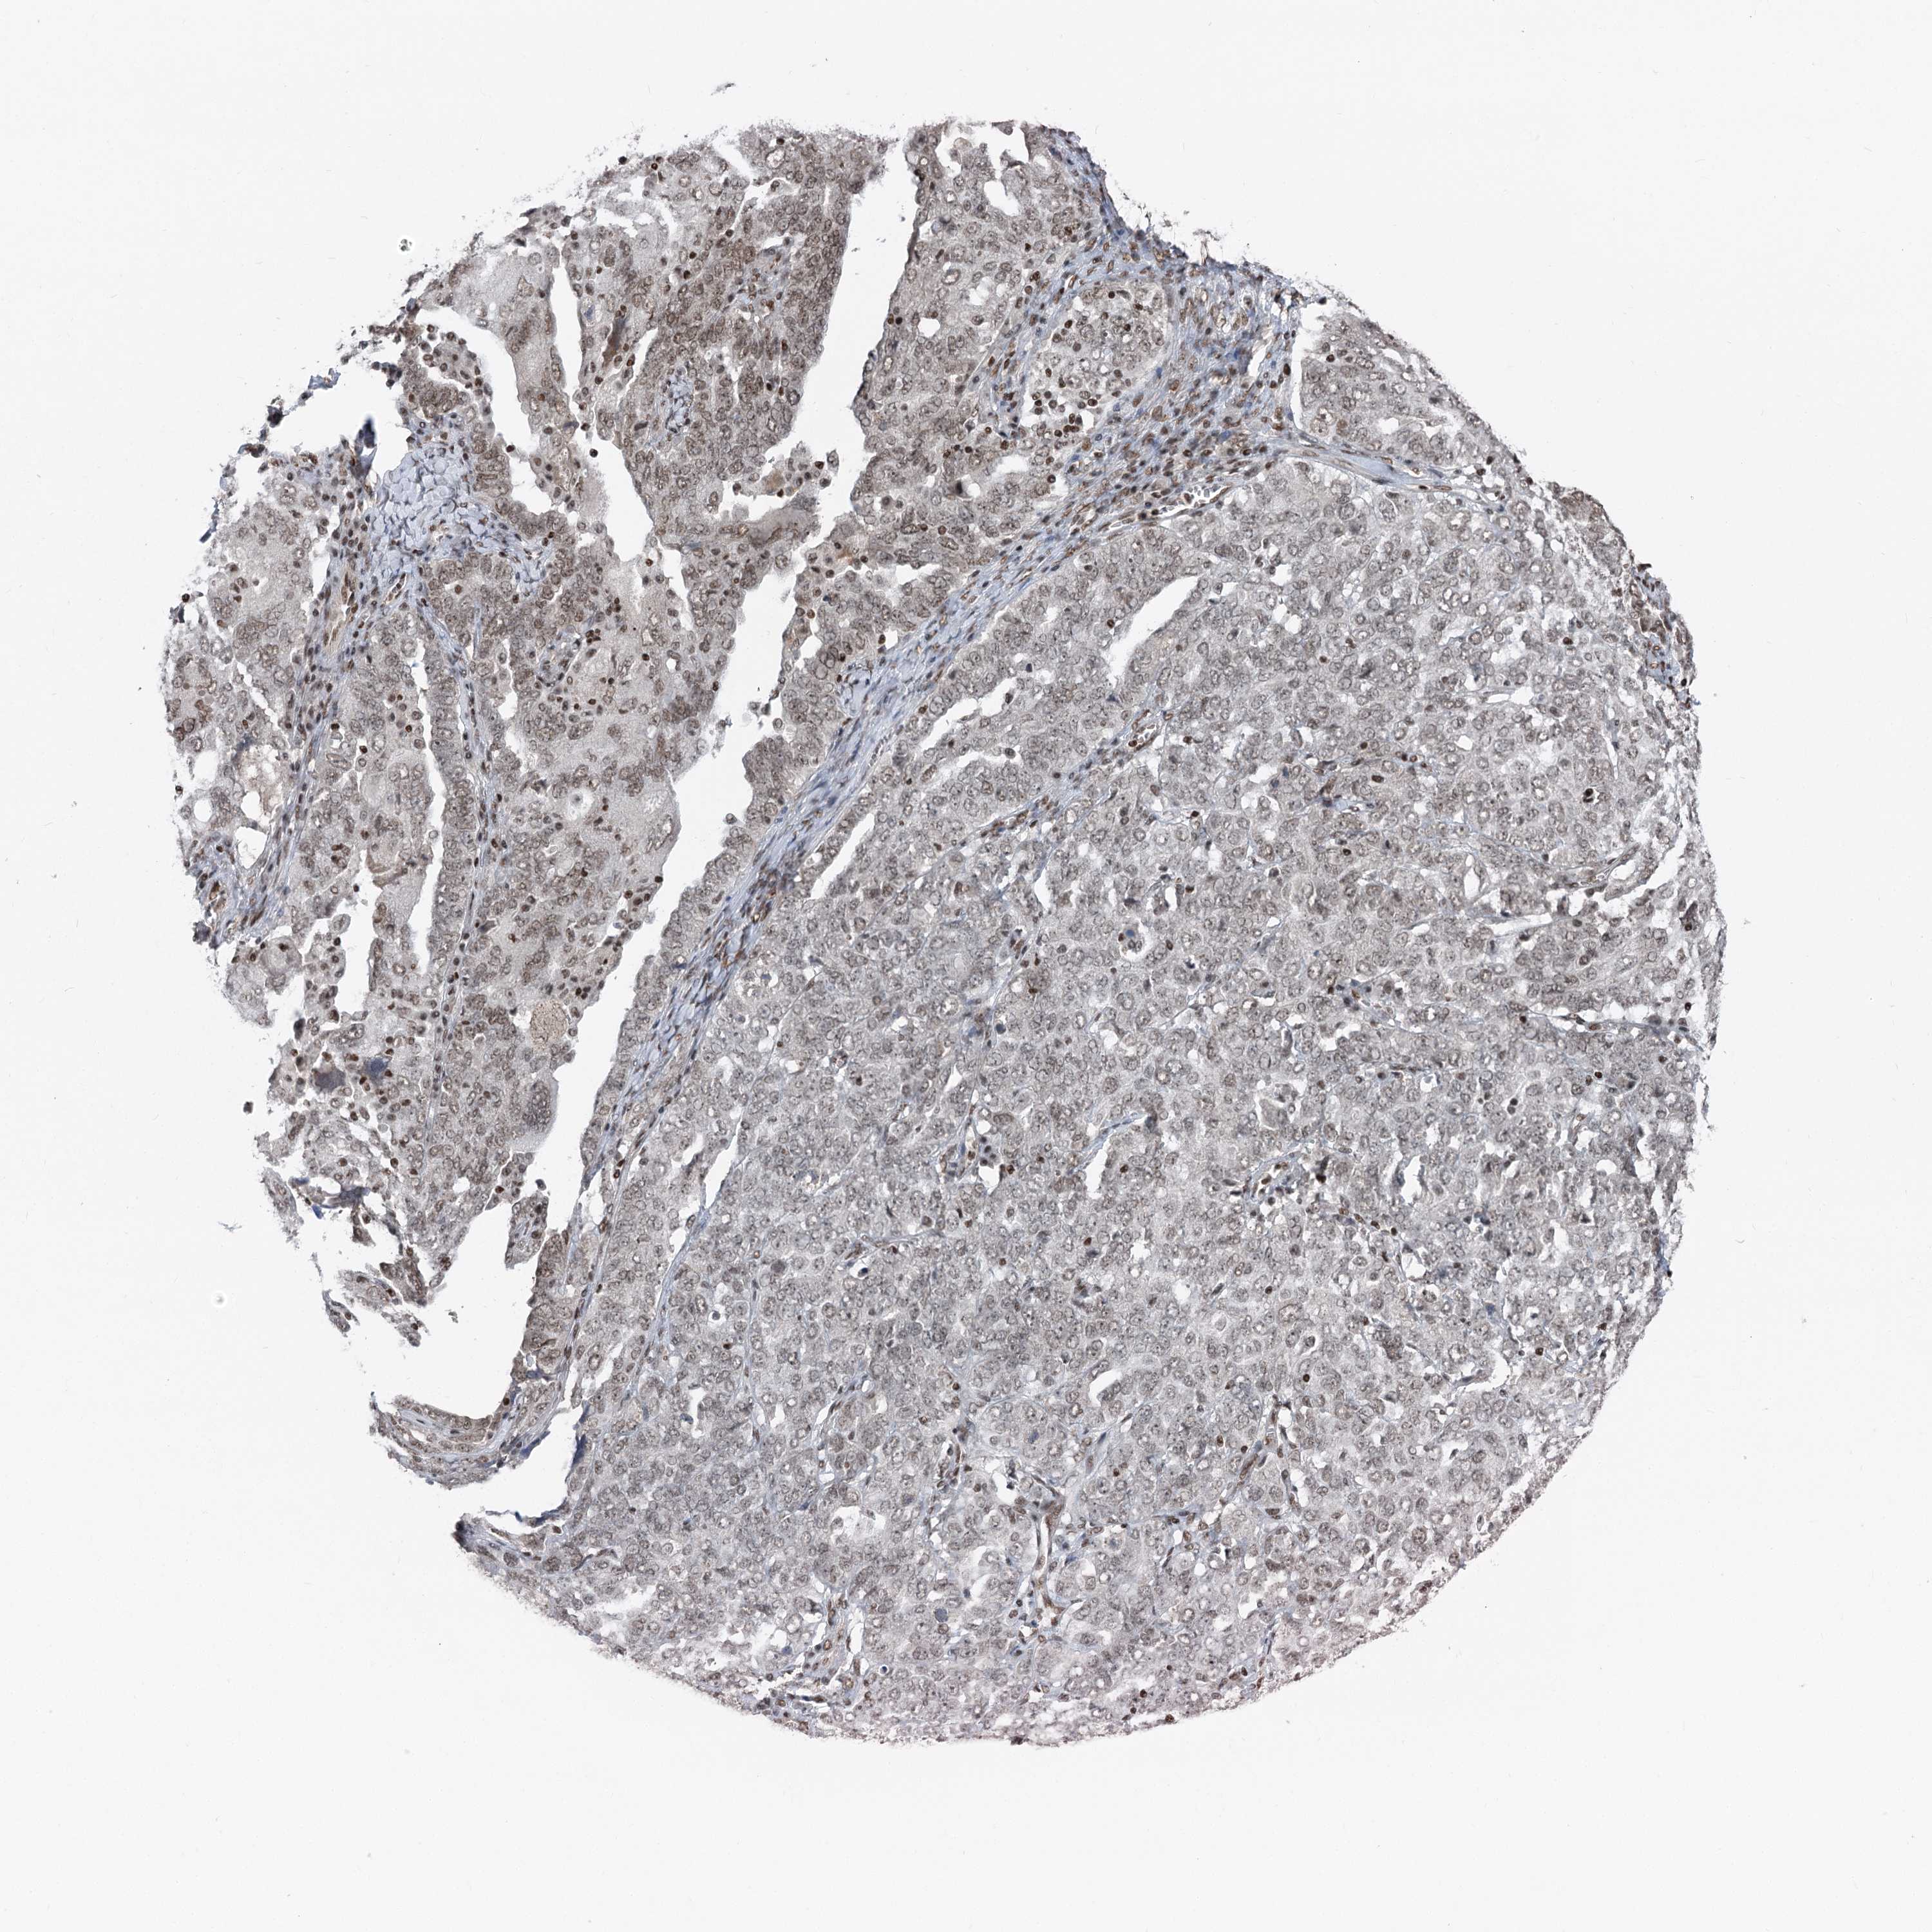

OVARIAN CANCER - Protein expressioni

A mouse-over function shows sample information and annotation data. Click on an image to view it in a full screen mode. Samples can be filtered based on level of antibody staining by selecting one or several of the following categories: high, medium, low and not detected. The assay and annotation is described here.

Note that samples used for immunohistochemistry by the Human Protein Atlas do not correspond to samples in the TCGA dataset.

Antibody stainingi

Antibody staining in the annotated cell types in the current human tissue is reported as not detected, low, medium, or high, based on conventional immunohistochemistry profiling in selected tissues. This score is based on the combination of the staining intensity and fraction of stained cells.

Each image is clickable and will lead to virtual microscopy that enables deeper exploration of all samples and also displays staining intensity scores, fraction scores and subcellular localization as well as patient and tissue information for each sample.

Antibody HPA035568

Antibody HPA037017

Staining

High

Medium

Low

Not detected

Intensity

Strong

Moderate

Weak

Negative

Quantity

>75%

75%-25%

<25%

None

Location

Nuclear

Cytoplasmic/membranous

Cytoplasmic/membranous,nuclear

Cystadenocarcinoma, serous, NOS

Carcinoma, endometroid

Cystadenocarcinoma, mucinous, NOS

Carcinoma, NOS